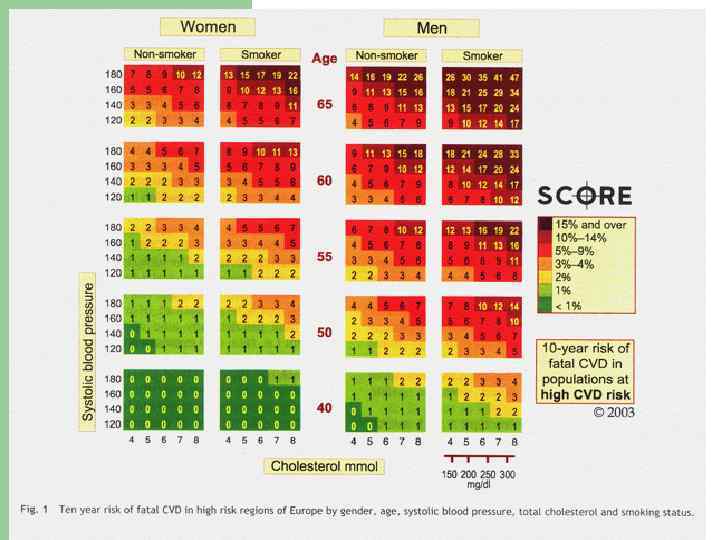

Профилактика ИБС 1. 2. Первичная(ещё нет ИБС, но есть ФР): - нейтрализация ФР, скриннинг здоровых лиц с ФР каждые 5 лет - аспирин 75 -150 мг при высоком риске ССО (шкала SCORE), статины при дислипидемии. Скрининг ИБС лицам определённых профессий Вторичная: - адекватная терапия ИБС и сопряжённой патологии

Шкала SCORE